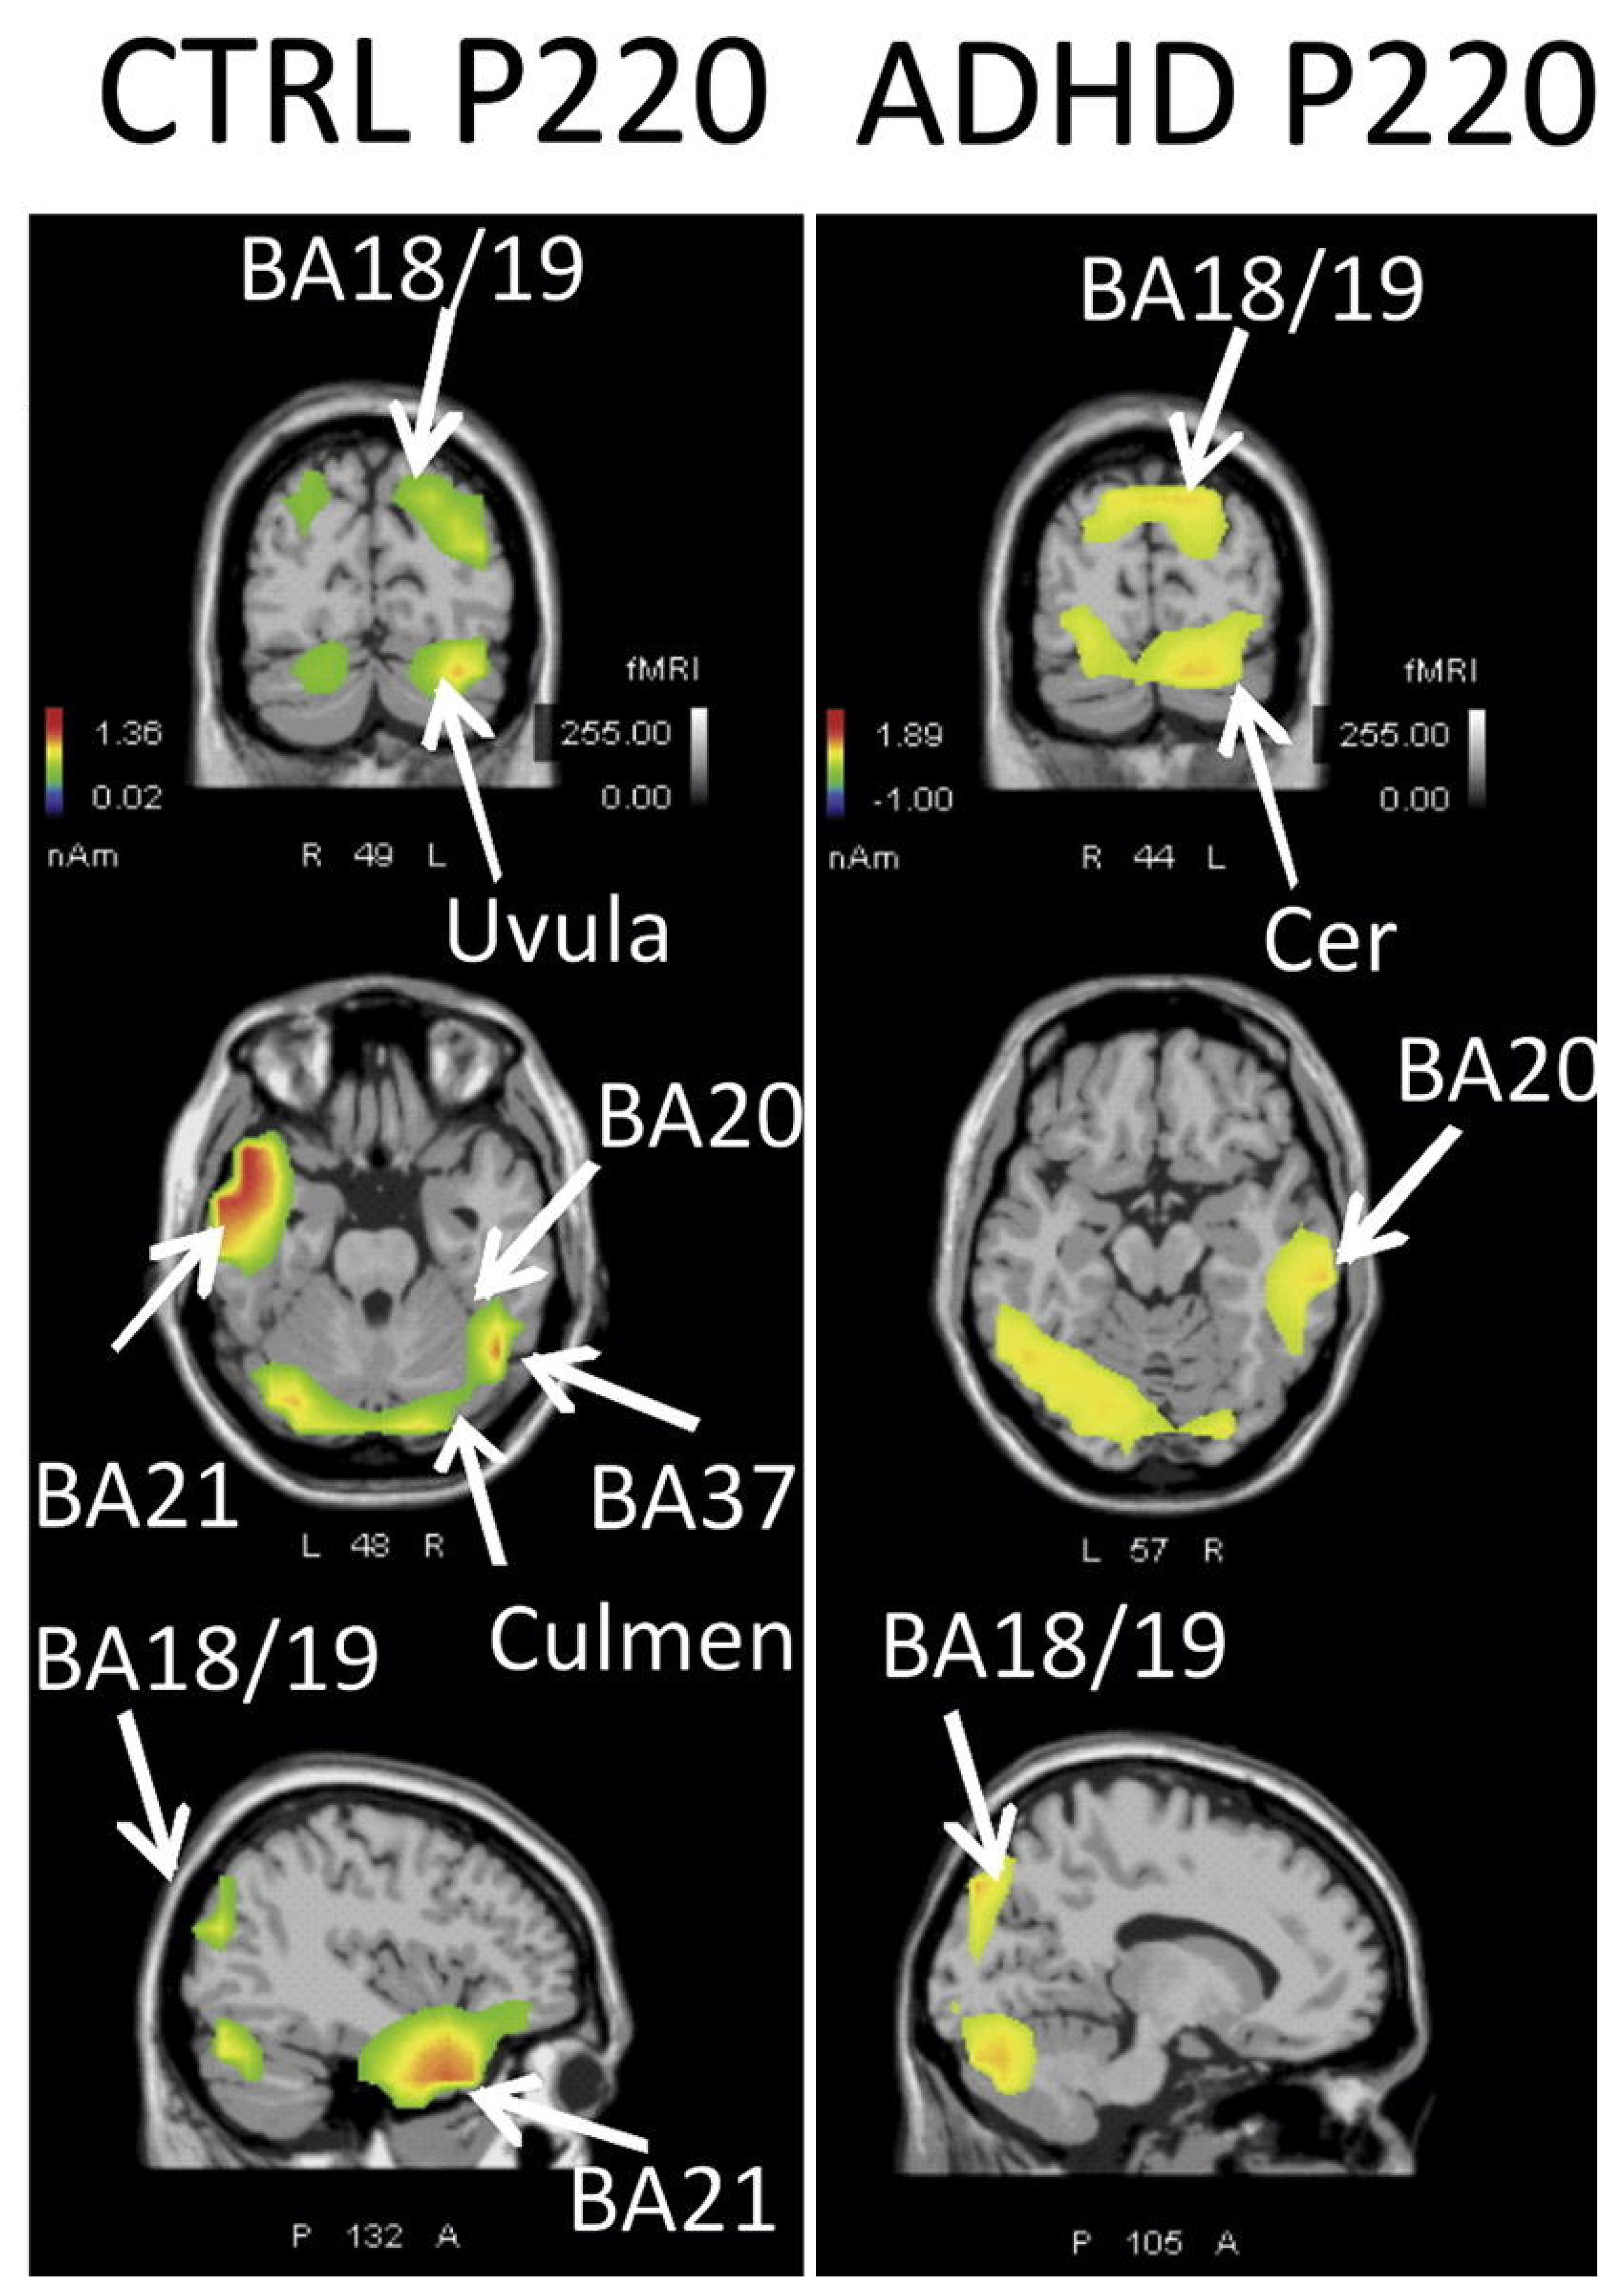

- Leroy, A.; Petit, G.; Zarka, D.; Cebolla, A.; Palmero-Soler, E.; Strul, J.; Dan, B.; Verbanck, P.; Cheron, G. EEG Dynamics and Neural Generators in Implicit Navigational Image Processing in Adults with ADHD. Neuroscience 2018, 373, 92–105. [Google Scholar] [CrossRef] [PubMed]